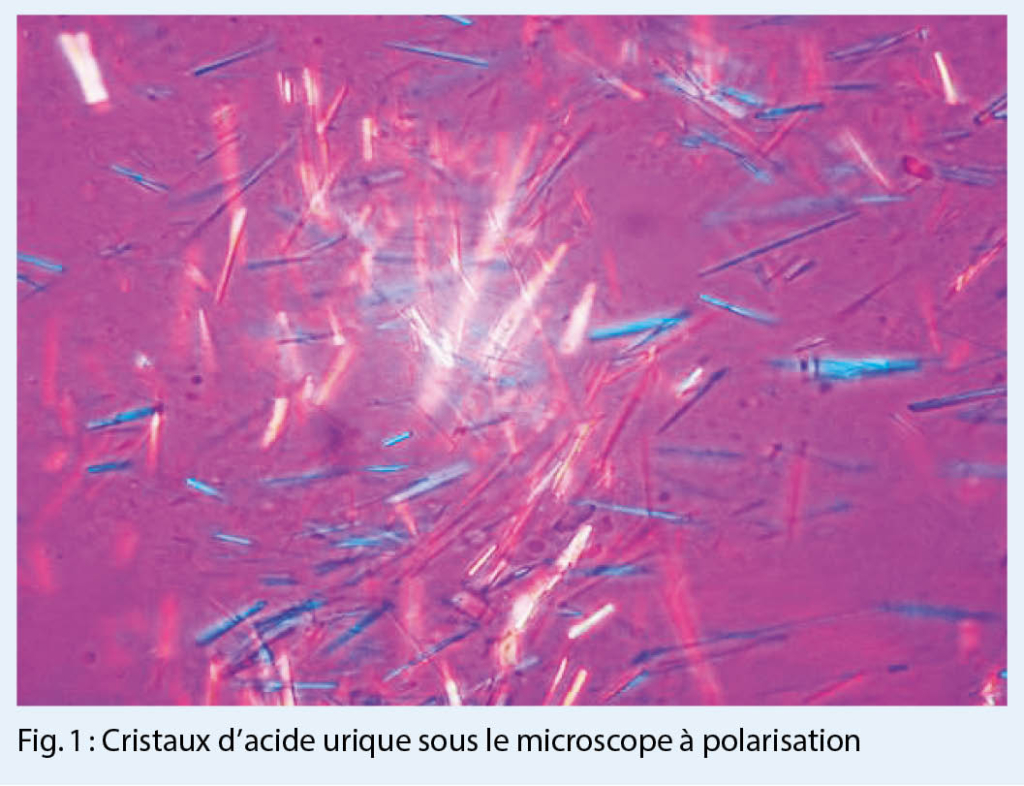

L’ arthrite goutteuse aiguë est généralement une monoarthrite qui se manifeste de façon suraiguë (avec des douleurs, des rougeurs et des gonflements importants) et affecte de préférence les membres inférieurs. Plus la clinique est typique, plus le diagnostic est probable. Cependant, le diagnostic différentiel doit toujours considérer une infection ou une pseudo-goutte (chondrocalcinose). Le gold-standard pour un diagnostic fiable reste la détection microscopique de cristaux d’ urates dans le prélèvement de l’ articulation affectée (fig. 1.) (ou celui du tissu) ou d’ identifier des dépôts d’ urates par échographie à haute résolution (fig. 2.) ou, à la rigueur, par tomodensitométrie à double énergie (les deux méthodes d’ imagerie sont très spécifiques, mais nécessitent un certain dépôt d’ urates pour être détectées et peuvent donc être faussement négatives, surtout dans les premiers stades).